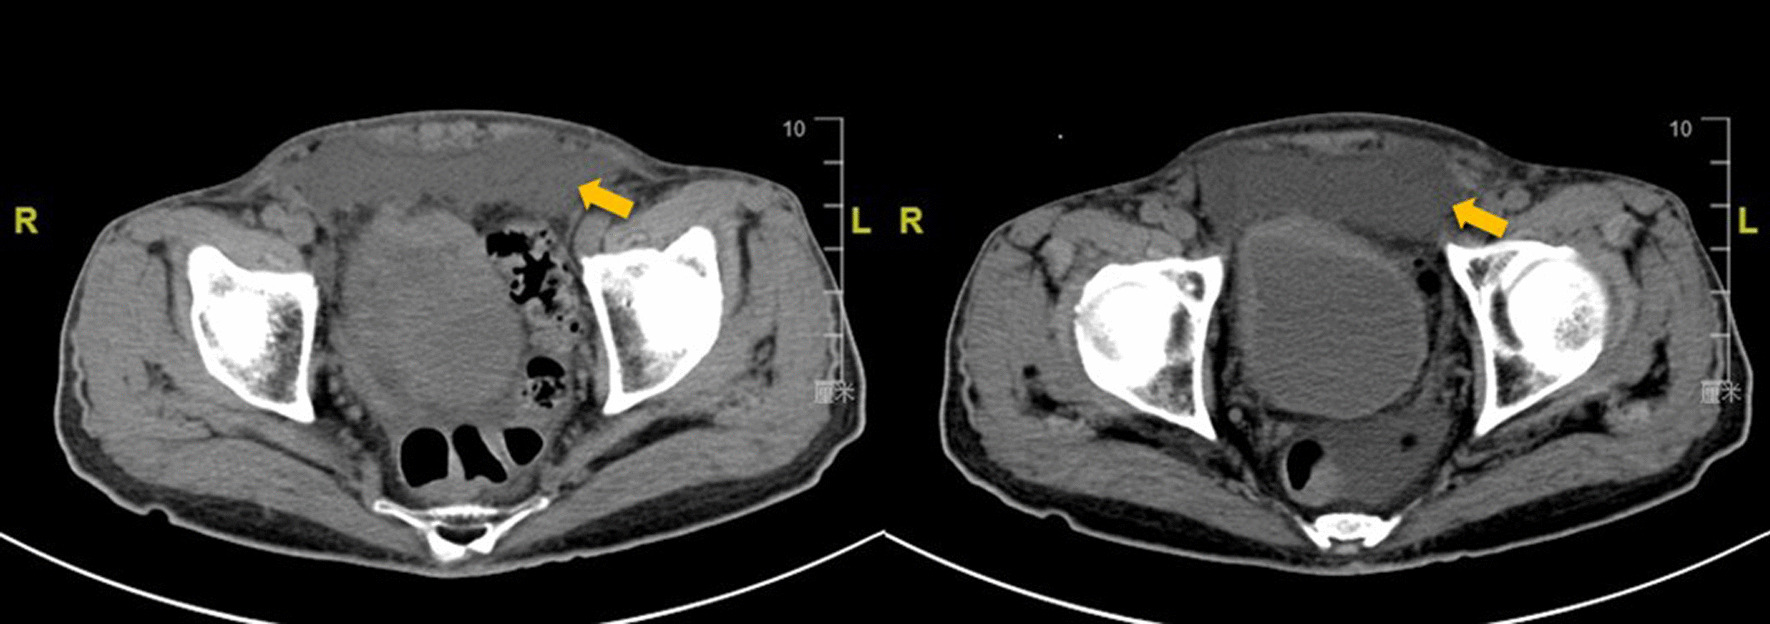

Although most seroma do not cause serious harm to patients, it is still a risk factor leading to other postoperative complications. In our study, the closed-suction drainage tube in the preperitoneal space was used to drain the accumulated fluid, which significantly relieved postoperative pain and reduced scrotal edema, urinary retention and other complications. Our findings are consistent with previous studies [25, 30, 31]. In addition, the postoperative complications also increased psychological burden on patients. In the present study, only one patient experienced severe pain and massive seroma formation after the operation. After conservative treatment failed, the second laparoscopic surgery was performed to drain the fluid in the preperitoneal space (Fig. 6). Therefore, we attempted to solve these clinical problems by placing the closed-suction drainage tube, which is a simple, inexpensive, and traditional method.

Fig. 6.

Fluid accumulation in the preperitoneal space